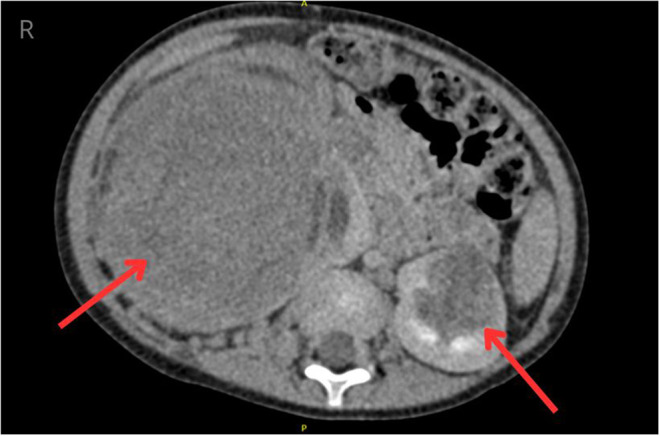

肾母细胞瘤(Wilms' tumor, WT)是儿童最常见的肾脏肿瘤。尽管它生长迅速,但它通常是无症状的。它最常见于3至5岁之间,在女孩中更为常见。大量研究报告了Wilms肿瘤的发生与遗传背景之间的联系。双侧肾母细胞瘤(BWT)的治疗提出了几个挑战。最近的研究提出了遗传对BWT发育的影响的问题。我们相信我们的病例报告是创新的,因为它提供了一种罕见的临床表现的信息,并全面地解决了遗传研究对有利治疗结果的潜在影响,这在文献中只进行了有限的详细讨论。病例描述涉及一名2岁和5个月大的患者,因腹部轮廓改变与其母亲一起就诊。在病史中,男孩的母亲曾接受过WT治疗。腹腔成像显示双肾存在病理性组织改变。在此基础上,诊断为V期Wilms肿瘤。男孩接受了右侧肿瘤肾切除术,随后左侧半肾切除术。他还接受了术前和术后化疗。基因检测显示WT1基因一个等位基因的外显子8和外显子9-10缺失。尽管对WT患儿的总体生存率数据乐观,但出现疾病复发和双侧BWT的患者仍存在一个重要的临床问题。这类患者通常需要根治性治疗,这将带来长期的后果。识别有家族性WT或BWT风险的患者允许相对早期的干预和有效的预防。此外,某些与WT相关的基因变异可以被认为是预后的生物标志物。

Wilms' tumor (WT) is the most common renal neoplasm in children. Despite its rapid growth, it is often asymptomatic. It most commonly occurs between the ages of 3 and 5, more frequently in girls. Numerous studies report an association between the occurrence of Wilms' tumor and genetic background. Treatment of bilateral Wilms' tumor (BWT) presents several challenges. Recent studies raise the issue of the influence of genetics on the development of BWT. We believe that our case report is innovative as it provides information on a rare clinical presentation and comprehensively addresses the potential impact of genetic studies on favorable treatment outcomes, which are discussed only in limited detail in the literature. The case description concerns a 2-year-old and a 5-month-old patient who presented with his mother due to a change in abdominal contour. In the medical history, the boy's mother had been treated for WT. Imaging of the abdominal cavity revealed the presence of pathological tissue changes in both kidneys. Based on this, stage V Wilms' tumor was diagnosed. The boy underwent a right-sided tumor nephrectomy followed by a left-sided heminephrectomy. He also received pre- and post-operative chemotherapy. Genetic testing revealed a deletion fragment of exon 8 and exons 9-10 on one allele of the WT1 gene. Despite optimistic data regarding overall survival in children with WT, a significant clinical issue remains with patients experiencing disease recurrence and bilateral BWT. Radical treatment is often required for such patients, which carries long-term consequences. Identifying patients at risk for familial WT or BWT allows for relatively early intervention and effective prevention. Furthermore, certain gene variants associated with WT can be considered prognostic biomarkers.